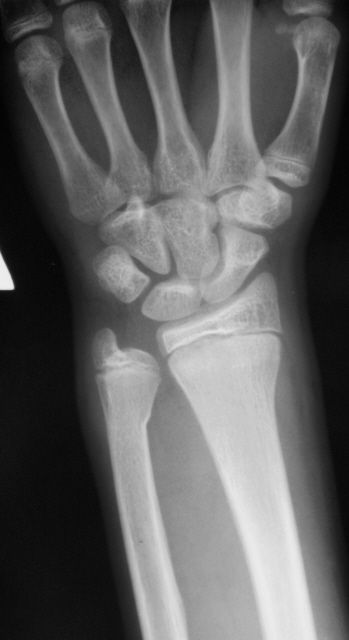

Случай № 4.

4. Остеоэпифизеолиз луча  в н/3 и перелом локтевой в н/3.

А я считаю,что в №4 поднадкостничный перелом обеих костей предплечья в н/3, в боковой проекции виден перелом лучевой кости.

Случай №4: Остеоэпифизеолиз дистальный лучевой кости, со смещением к тылу до 10мм. Перелом шейки локтевой кости, поднадкостничный, с незначительным смещением.